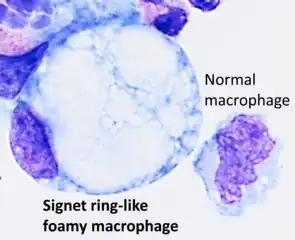

Gastric signet ring cell carcinoma. H&E stain. A signet ring-like foamy macrophage, which may mimic a cancer cell, but the texture of the nucleus is similar to that of a normal macrophage.

A signet ring-like foamy macrophage, which may mimic a cancer cell, but the texture of the nucleus is similar to that of a normal macrophage. High magnification micrograph showing signet ring cells, with clear cytoplasm, in metastatic breast carcinoma. H&E stain.